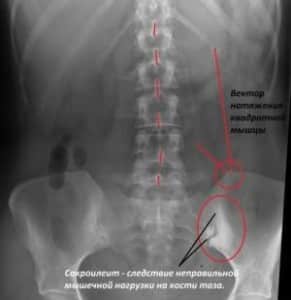

- Рентгенография.

Основным методом исследования, который является лакмусовой бумажкой в диагностике послеродовых травм и поражений связочного аппарата таза, остается рентгенография. Именно благодаря ей можно поставить такие диагнозы, как «симфизит», «разрыв сочленений», «перелом и вывих копчика», «сакроилеит».

По рентгенологическим данным выделяют 3 стадии, или степени тяжести, симфизита:

- I стадия – расстояние между тазовыми костями от 0,5 см до 1 см;

- II стадия – от 1 см до 1,9 см;

- III стадия – больше 2 см.

При увеличении расстояния более 2-3 см стоит задумываться о разрыве лонного сочленения.